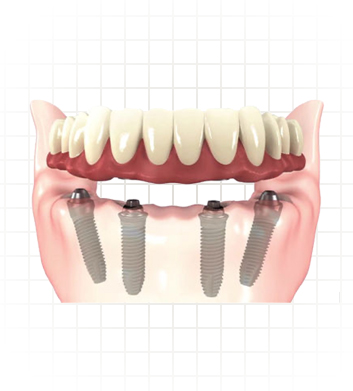

Hybrid Denture

Hybrid implant denture is a combination between both dental implants and traditional dentures. Hybrid denture is a full set of replacement teeth resting on dental implants (implant supported denture). With the arrival of the solid zirconia full-arch implant retained prosthesis we now have a prosthetic option that offers the stability and performance of dental implants with better cost.

Avoiding disadvantages of conventional dentures, hybrid dentures give better, non-fake appearance and are easier to maintain. Just like your natural teeth you need to brush them twice daily. Hybrid dentures are designed to be securely fit, fixed in place and permanent so they can only be removed by the dentist.